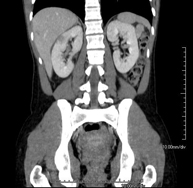

Prova diagnòstica que consisteix en l'estudi de l'abdomen d'alta definició anatòmica (fetge, vesícula biliar, via biliar, pàncrees, melsa, estómac, intestins, ronyons, estructures vasculars, bufeta, úter i ovaris, etc.) mitjançant l'ús d'un equip de TC (Tomografia Computeritzada). Aquestes imatges s'estudien posteriorment en una estació de treball que permet obtenir reconstruccions bidimensionals en diferents plànols de l'espai i també reconstruccions 3D (volumètriques). La majoria d'estudis requereixen l'ús de contrast iodat per millorar la definició de les imatges. - TC Pelvis

Prova diagnòstica que consisteix en obtenir imatges bi i tridimensionals de l'abdomen d'alta definició anatòmica (estructures òssies, estructures vasculars, fetge, pàncrees, vesícula biliar, ronyons, glàndules suprarenals, melsa, intestí prim i gros, bufeta, úter i ovaris, pròstata i vesícules seminals, urèters, etc.) mitjançant l'ús d'un equip de TC (Tomografia Computeritzada). La majoria d'estudis requereixen l'ús de contrast iodat. - TC Fetge

Prova diagnòstica que consisteix en obtenir imatges bi i tridimensionals del ronyó i del sistema urinari d'alta definició anatòmica mitjançant l'ús d'un equip de TC (Tomografia Computeritzada). Es realitza l'estudi abans i després de l'ús de contrast iodat en diferents "fases renals" per a una valoració funcional i anatòmica: parènquima renal, urèters, bufeta urinària, artèries i venes renals, etc. així com les estructures adjacents (vena cava inferior, aorta abdominal, fetge, melsa, etc.). Està especialment indicat quan hi ha sospita de lesions renals, en pacients amb sang a l'orina o hematúria, etc. - TC Urològic